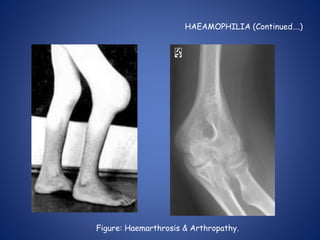

HAEAMOPHILIA (Continued….)

LONG TERM COMPLICATIONs

COMPLICATION due to repeated

hemorrhage:

– Arthropathy of large joints eg knee, elbow

– Muscle atrophy due to haematoma

– Mononeuropathy due to pressure of

haematoma.

COMPLICATION due to therapy

– Antifactor VIII antibody develops.

– Virus transmission Hepatitis B,C + HIV etc.

Figure: Haemarthrosis & Arthropathy.